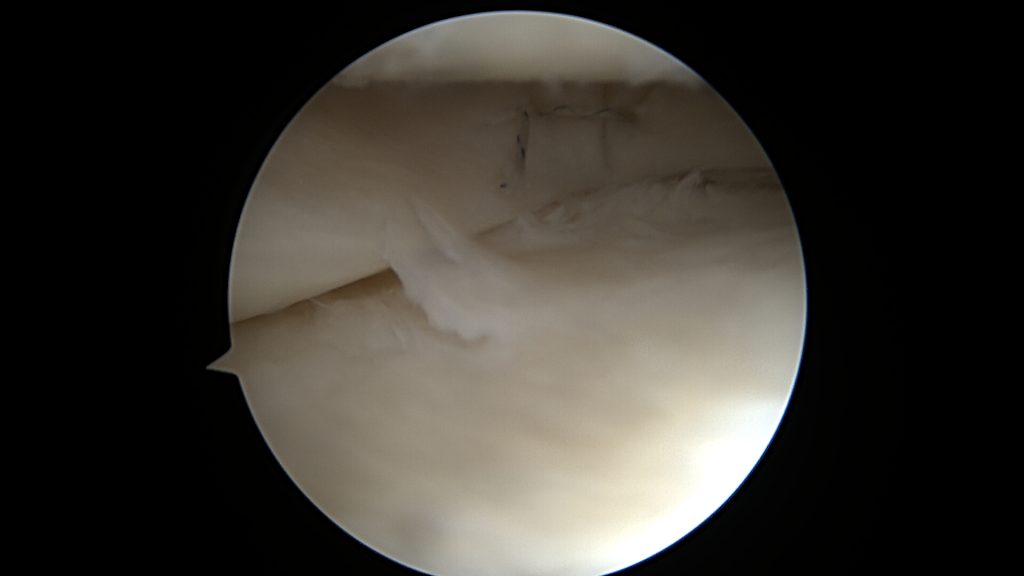

Jeśli jednak w trakcie urazu ulegnie ona większemu uszkodzeniu, rozkawałkowaniu, lub gdy będziemy zwlekać z zabiegiem operacyjnym, to po wprowadzeniu optyki do stawu naszym oczom ukaże się łąkotka rozwłókniona, popękana, w kilku kawałkach.

W tym przypadku jej proste przyszycie nie będzie możliwe, nie będzie po prostu stabilnych fragmentów łąkotki które można złapać szwem. Konieczne jest zastosowanie techniki „biokanapki”. Zabieg polega na owinięciu błoną kolagenową uszkodzonego fragmentu łąkotki, błona pełni tu rolę worka trzymającego włókna łąkotki razem. Szwy zakłada się poprzez błonę kolagenową stabilizując tym samym luźne uszkodzone fragmenty łąkotki. Na koniec zabiegu podaje się komórki macierzyste do środka stworzonej w ten sposób przestrzeni. Postępowanie pozabiegowe jest w tym przypadku określone odpowiednim protokołem rehabilitacyjnym.